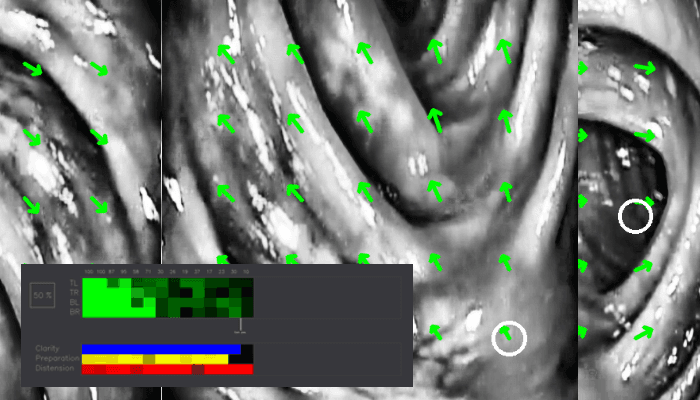

The software used classical computer vision techniques to asses multiple ways of measuring the quality of the examination. Clarity of the image, how well the patient has been prepared and so on. The most challenging part was a map that was going to approximate directly doctor’s technique in operating the endoscope.

For that optical flow was used to calculate the distance traveled by the endoscope in patient’s body and a map was outputted real time that approximated the examined parts of the colon.